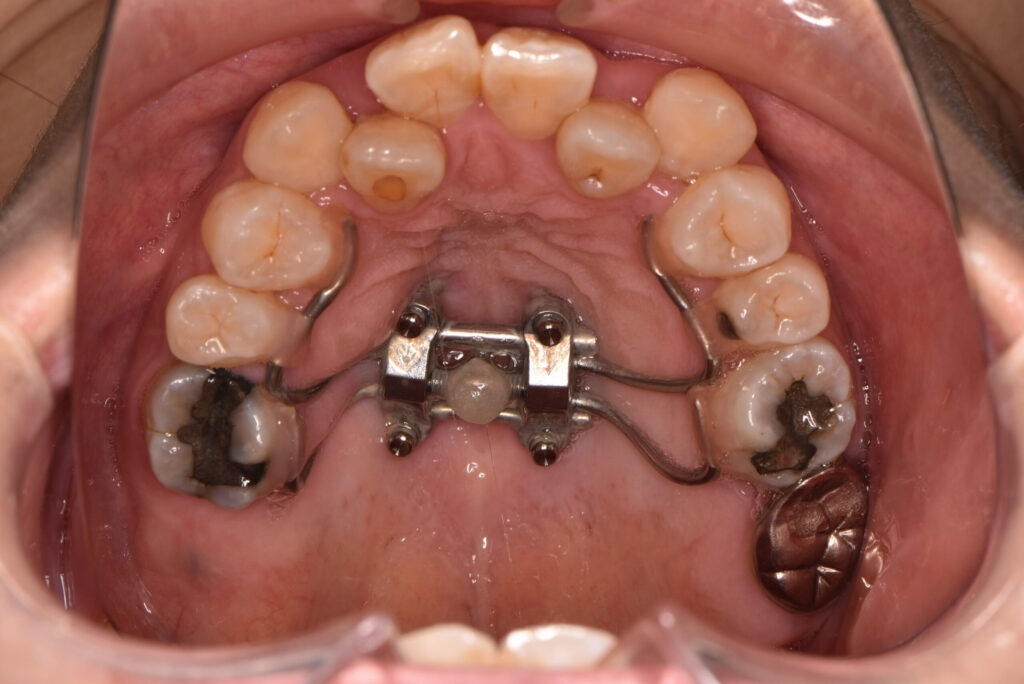

■ 急速拡大装置(きゅうそくかくだいそうち)

真ん中にネジのような部分があり、1日に1~2回回すことで、短い期間(2~3週間)で一気にあごを広げます。子どもの場合は、あごの骨がまだ柔らかいため効果が出やすいです。

装置は、主に奥歯にバンドのような金具を取りつけて固定されます。

そこからスクリュー(拡大専用のネジ)やワイヤーで力を加えて、左右のあごの骨を広げていきます。

症例紹介

| 主訴 | 受け口、歯のデコボコ |

| 診断名 | 叢生 |

| 年齢 | 40代女性 |

| 治療内容 | マルチブラケット装置、MSE |

| 抜歯・非抜歯 | 抜歯 |

| 治療期間 | 動的治療21ヶ月 |

| 費用 | 総額¥975000(改正前の金額) (相談料、検査料、診断料、動的治療費、保定期間料) ※自由診療になります |

| リスク・副作用 | 歯痛、虫歯、歯周病、口内炎、発音障害、歯根吸収、歯肉退縮、歯髄炎、顎関節症、歯の咬耗、エナメルクラック |